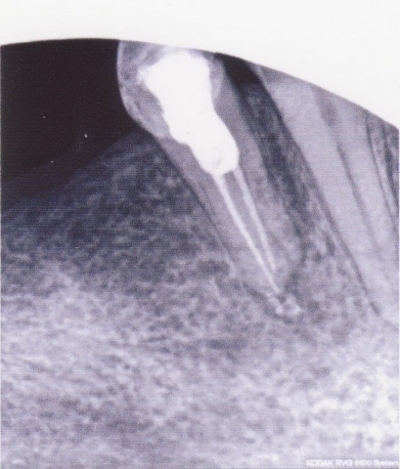

Примеры лечения радикулярных кист челюстей без скальпеля:

Фото: после лечения депофорезом

Фото: до лечения депофорезом